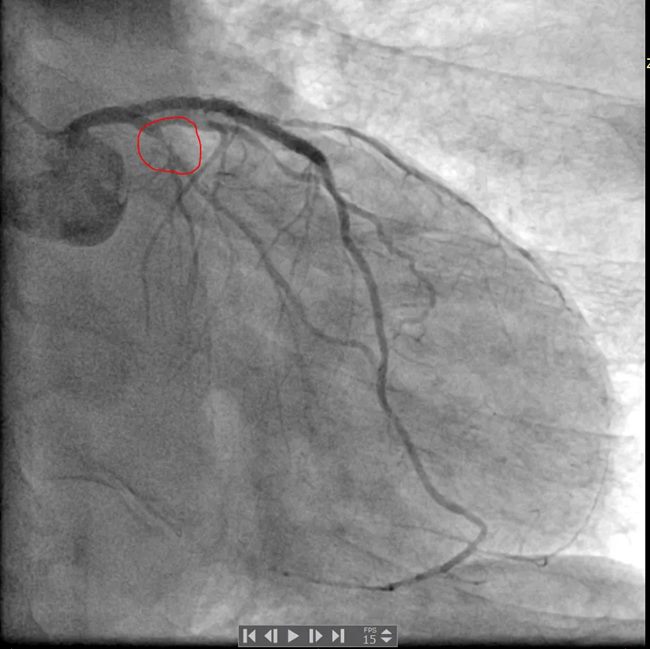

冠脉造影结果显示:左主干未见明显异常,前降支近中段可见支架影,近段支架内狭窄50%,前向血流TIMI3级;回旋支近段次全闭塞,前向血流TIMI2-3级;右冠中段弥漫性狭窄,最重处狭窄95%,前向血流TIMI3级。

最终由手术医师为买买提做了介入治疗:右冠置入支架1枚,回旋支置入药物球囊1枚。